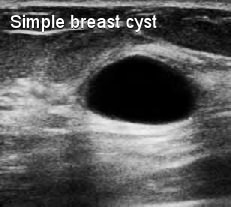

Kista payudara adalah kantung berisi cairan di dalam jaringan payudara dan akan muncul sebagai benjolan payudara. Baik kista payudara maupun penyakit payudara fibrokistik adalah lesi jinak dan tidak berkembang menjadi kanker payudara dan tidak meningkatkan risiko kanker.

Kista payudara yang kompleks yang mengandung campuran jaringan padat di dalam kista payudara mungkin memiliki risiko perubahan ganas, oleh karena itu perlu diselidiki dan dipantau.